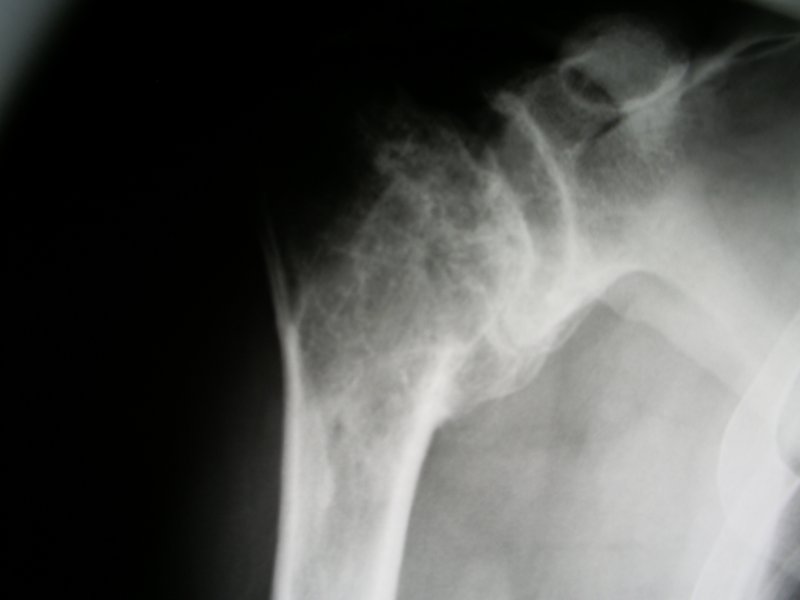

Lata po upadku na bark pojawila sie artroza.

Złamanie główki kości ramiennej z całkowita destrukcja, która uniemożliwila rekonstrukcję i spowodowała konieczność implantacji endoprotezy. Przy zachowanych przyczepach mieśni obręczy kończyny górnej została zastosowana standartowa endoproteza.